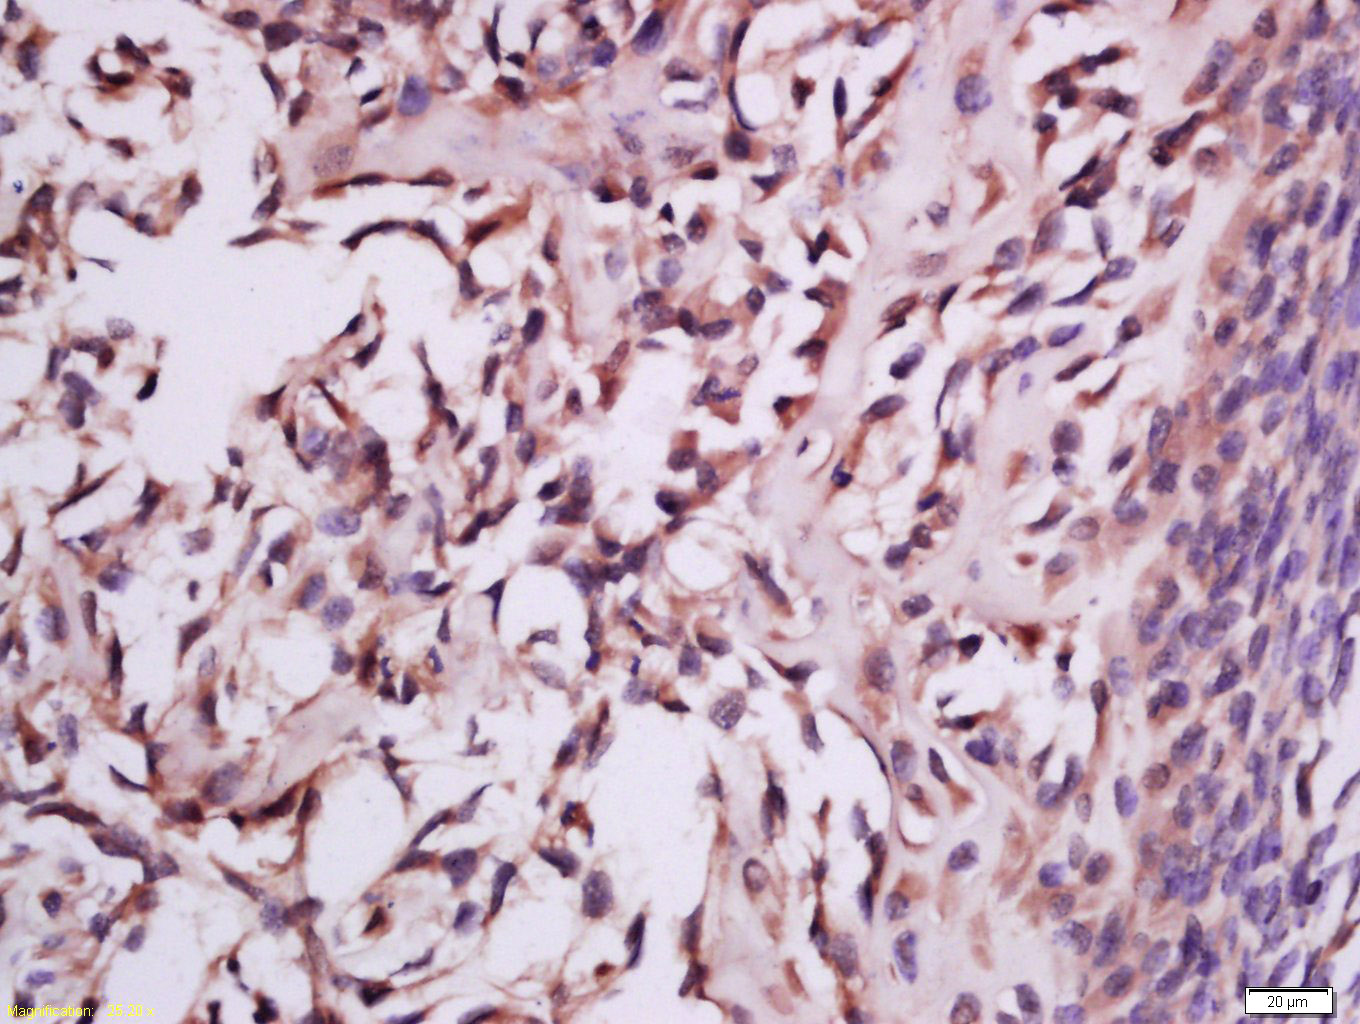

Tissue/cell: mouse embryo tissue; 4% Paraformaldehyde-fixed and paraffin-embedded; Antigen retrieval: citrate buffer ( 0.01M, pH 6.0 ), Boiling bathing for 15min; Block endogenous peroxidase by 3% Hydrogen peroxide for 30min; Blocking buffer (normal goat serum,C-0005) at 37℃ for 20 min; Incubation: Anti-MSRB2 Polyclonal Antibody, Unconjugated(bs-17861R) 1:200, overnight at 4°C, followed by conjugation to the secondary antibody(SP-0023) and DAB(C-0010) staining

Tissue/cell: rat brain tissue; 4% Paraformaldehyde-fixed and paraffin-embedded; Antigen retrieval: citrate buffer ( 0.01M, pH 6.0 ), Boiling bathing for 15min; Block endogenous peroxidase by 3% Hydrogen peroxide for 30min; Blocking buffer (normal goat serum,C-0005) at 37℃ for 20 min; Incubation: Anti-MSRB2 Polyclonal Antibody, Unconjugated(bs-17861R) 1:200, overnight at 4°C, followed by conjugation to the secondary antibody(SP-0023) and DAB(C-0010) staining

Paraformaldehyde-fixed, paraffin embedded (mouse kidney); Antigen retrieval by boiling in sodium citrate buffer (pH6.0) for 15min; Block endogenous peroxidase by 3% hydrogen peroxide for 20 minutes; Blocking buffer (normal goat serum) at 37°C for 30min; Antibody incubation with (MSRB2) Polyclonal Antibody, Unconjugated (bs-17861R) at 1:200 overnight at 4°C, followed by operating according to SP Kit(Rabbit) (sp-0023) instructionsand DAB staining.